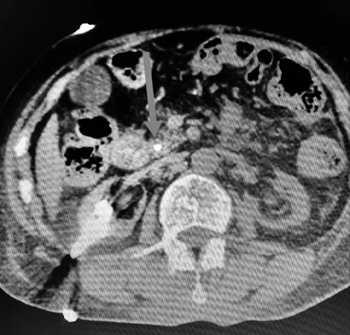

大年初一,北京积水潭医院回龙观院区消化内科病房内,一位慢性腹泻,考虑放射性结肠炎的患者,突发右上腹痛,严重黄疸,CT提示胆总管结石,胆总管扩张,胆囊炎。患者曾患有妇科恶性肿瘤,放化疗后,双肾造瘘,尿毒症透析。在这样的基础病上突发急性梗阻性黄疸,急性胆管炎,病情复杂。复查化验总胆红素达到250umol/L(直接胆150umol/L),其他重要指标也是急转直下,血小板降至三万,PA降至30多……病情危急!

科室经过简短讨论后,决定给予患者引流减黄治疗。虽然不排除存在放射性胆管炎,做ERCP内引流的难度较大,但由于患者血小板及凝血功能均差,经皮经肝的外引流创伤出血风险更大,遂决定还是首先尝试十二指肠镜下内引流。